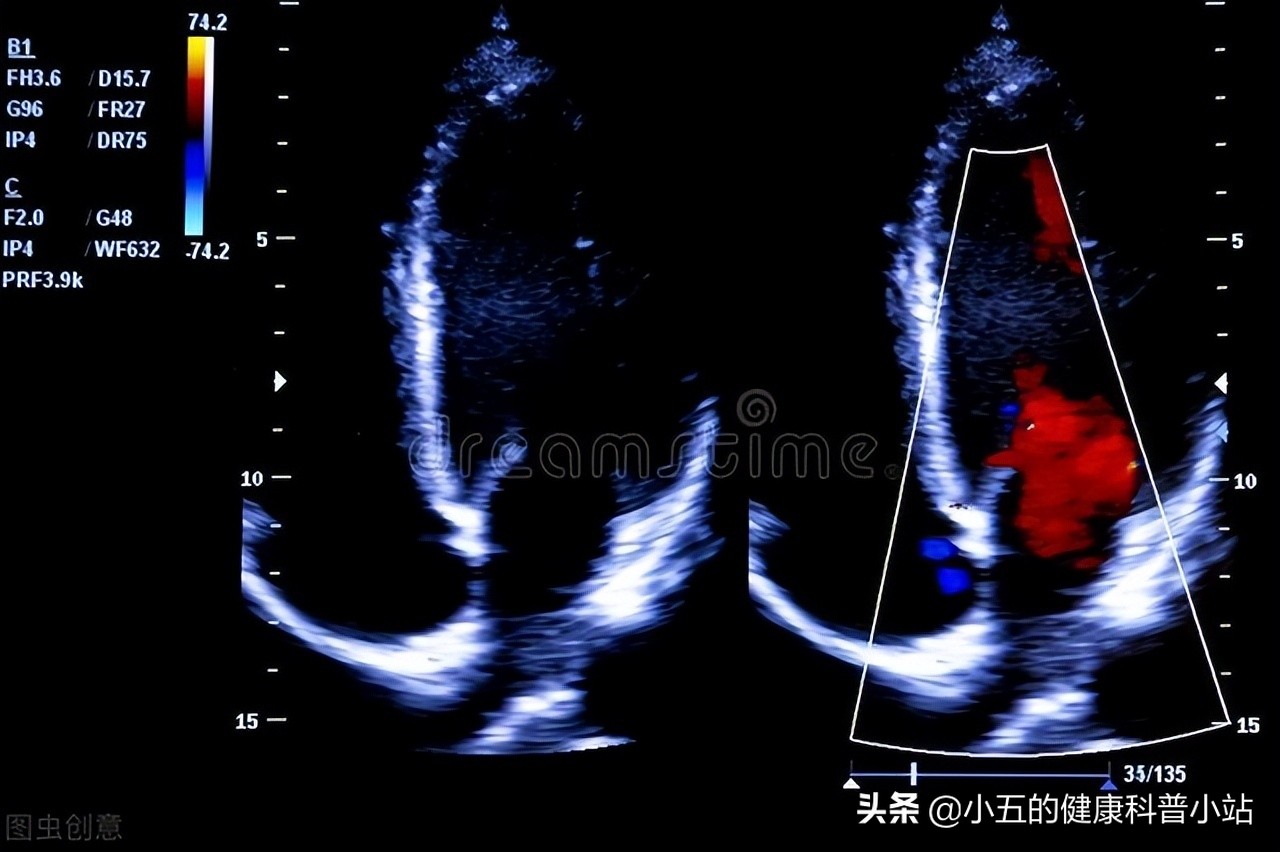

医生通过对王大爷的心脏进行检查后发现他心脏的 射血分数只有42% ,结合他的临床症状,诊断其为 II级心功能衰竭 ,并且给他开具 了两种药呋塞米和螺内酯 ,医生嘱咐王大爷这2种药都是利尿药,可以配合他原本的降压药一起服用,王大爷很不解,询问医生为什么要开两种利尿药,一种不行吗? 医生解释道呋塞米和螺内酯虽然都有利尿效果,但是它们的作用机制不同,单用一种会非常容易引起血钾水平的紊乱,联合使用不仅可以增加疗效,而且可以减少副作用 ,并且嘱咐王大爷每过1个月左右复查一次电解质,防止不良反应,王大爷答应了。

2、抑制心肌纤维化,保护心脏和血管

螺内酯的第二个作用机制就是抑制心肌间质纤维化,保护心脏功能。现代研究表明醛固酮激素对于心脏纤维化具有明显的诱导作用,其可以降低心肌细胞的顺应性,增加心肌的僵硬程度,同时会导致心脏的收缩和舒张功能降低,导致射血分数、心输出量等心脏的关键功能下降,从而导致心力衰竭。 螺内酯通过与醛固酮发生竞争性抑制作用,抑制醛固酮对于心肌细胞和血管的病理作用,减少心脏中胶原蛋白的合成,抑制心肌纤维化,从而有效保护心脏功能,临床上常将其作为治疗慢性心衰的常用药之一 。